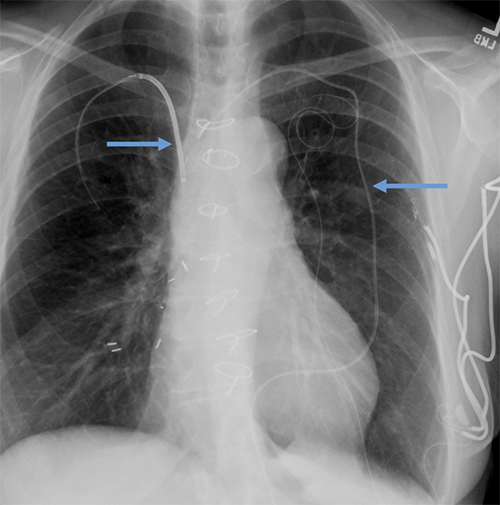

- CEID images with lead types:

Pacemaker with transvenous leads

Pacemaker with epicardial leads

Defibrillator lead

Subcutaneous defibrillator

Cut epicardial wires (often hard to see)

Abandoned leads

Abanded leads plus generator

Temporary transvenous lead

Leadless pacemaker